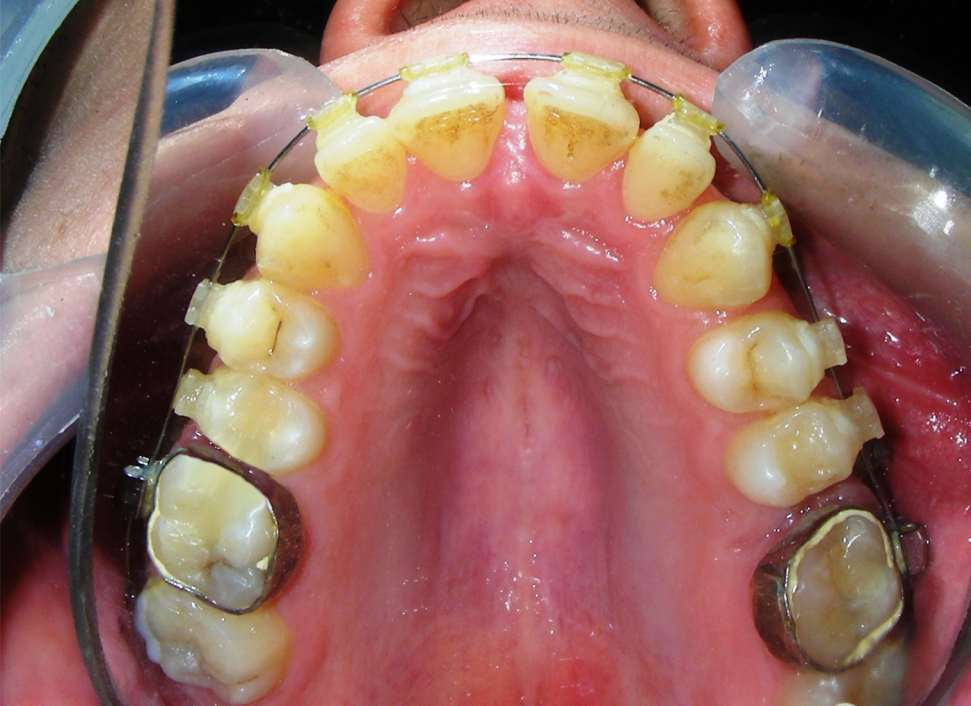

Was installed a Hyrax-type 10mm palatal expander of the Brazilian trademark Morelli® , modified by the author to be adapted to receive TADs microscrews, in order to initiate maxillary disjunction with MARPE (Mini-implant Assisted Rapid Palatal Expansion), TADS was installed with skeletal anchorage placed bilaterally having as references the roots of the maxillary canines and first premolars. Prior to insertion, local infiltrative anesthesia was administered using 2% lidocaine hydrochloride with 1:100,000 epinephrine. A total dose of approximately 0,8 mL per side (cortical infiltration technique). The TADs were inserted under aseptic conditions using a manual driver. Microscrew Evolution 1,6 Ø x 10 mm from the Argentine brand Odontit® . The Hyrax expander was then fitted and activated after 48 hrs .

Protocol of one activation per day was followed for a period of three weeks where the first clinical and radiographic evaluation was performed, showing clear signs of skeletal expansion, including the presence of a midline diastema. One more week of activations was added with a total of 28. The patient reported moderate headache during the first week of activation.

Having successfully achieved the expansion, we proceed to the intrusion of the posterior superior sectors, modifying the Hyrax by adding anchoring hooks at the buccal level of the first premolars. Using the Hyrax as anchorage, we sought a parallel intrusion. This could be replaced by a palatal bar. TADs were installed bilaterally at the mesial level of the first molars, inserting them as parallel as possible to the roots.

Simultaneously we begin with the alignment of the lower arch ,Simultaneously we began with the alignment of the lower arch with Roth prescription ceramic braces .022 . Henry Schein®

As the reader may infer, alignment and leveling of the upper anterior segment are being intentionally deferred at this stage of treatment. This strategic decision is based on the primary objective of closing the anterior open bite not through anterior extrusion, but by means of controlled posterior intrusion. This biomechanical approach promotes a counterclockwise rotation of the mandible, which leads to a increase in the facial axis angle and improvement in vertical facial proportions. By avoiding early anterior alignment, we prevent any premature vertical displacement of the upper incisors.